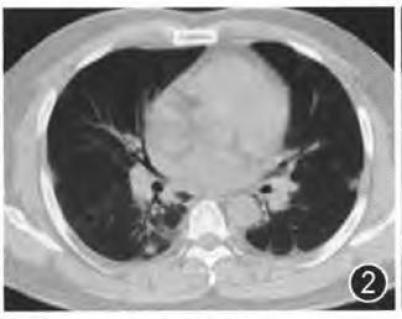

下面这个患者,右下叶病灶,既无磨玻璃,又不在胸膜下,依靠CT诊断新冠肺炎几乎不可能。